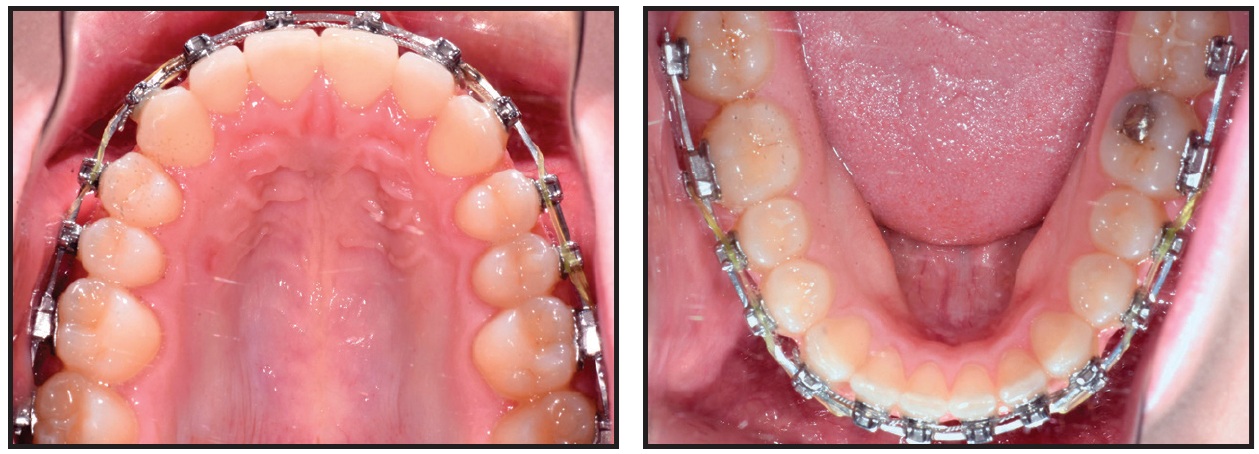

After 20 weeks of treatment, the rotations were corrected and proper alignment was achieved (Fig. 12). The bite turbos were removed, and .021" × .025" Insignia custom Copper NiTi archwires were placed for finishing in both arches.

Fig. 12 Case 2. After 20 weeks, SmartArch treatment completed, bite turbos removed, and Insignia* treatment started.

Case 2 illustrates the combined efficiency of the SmartArch and Insignia systems. Accurate bracket placement, with appropriate forces applied to each tooth, created a synergistic biological response. We were able to insert finishing archwires for detailing and occlusal refinement after only five months of treatment.